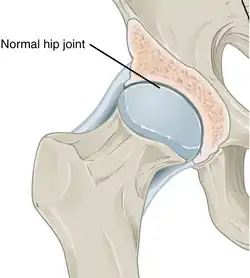

Annotated illustration of healthy hip joint

Healthy hip joint

While osteoarthritis is a degenerative joint disease that may cause gross cartilage loss and morphological damage to other joint tissues, more subtle biochemical changes occur in the earliest stages of osteoarthritis progression. The water content of healthy cartilage is finely balanced by compressive force driving water out and hydrostatic and osmotic pressure drawing water in.[37][38] Collagen fibres exert the compressive force, whereas the Gibbs–Donnan effect and cartilage proteoglycans create osmotic pressure which tends to draw water in.[38]

However, during the onset of osteoarthritis, the collagen matrix becomes more disorganized, and there is a decrease in proteoglycan content within cartilage. The breakdown of collagen fibers results in a net increase in water content.[39][40][41][42][43] This increase occurs because whilst there is an overall loss of proteoglycans (and thus a decreased osmotic pull),[40][44] it is outweighed by a loss of collagen.[38][44]

Other structures within the joint can also be affected.[45] The ligaments within the joint become thickened and fibrotic, and the menisci can become damaged and wear away.[46] Menisci can be completely absent by the time a person undergoes a joint replacement. New bone outgrowths, called "spurs" or osteophytes, can form on the margins of the joints, possibly in an attempt to improve the congruence of the articular cartilage surfaces in the absence of the menisci. The subchondral bone volume increases and becomes less mineralized (hypo mineralization).[47] All these changes can cause problems functioning. The pain in an osteoarthritic joint has been related to thickened synovium[48] and to subchondral bone lesions.[49]